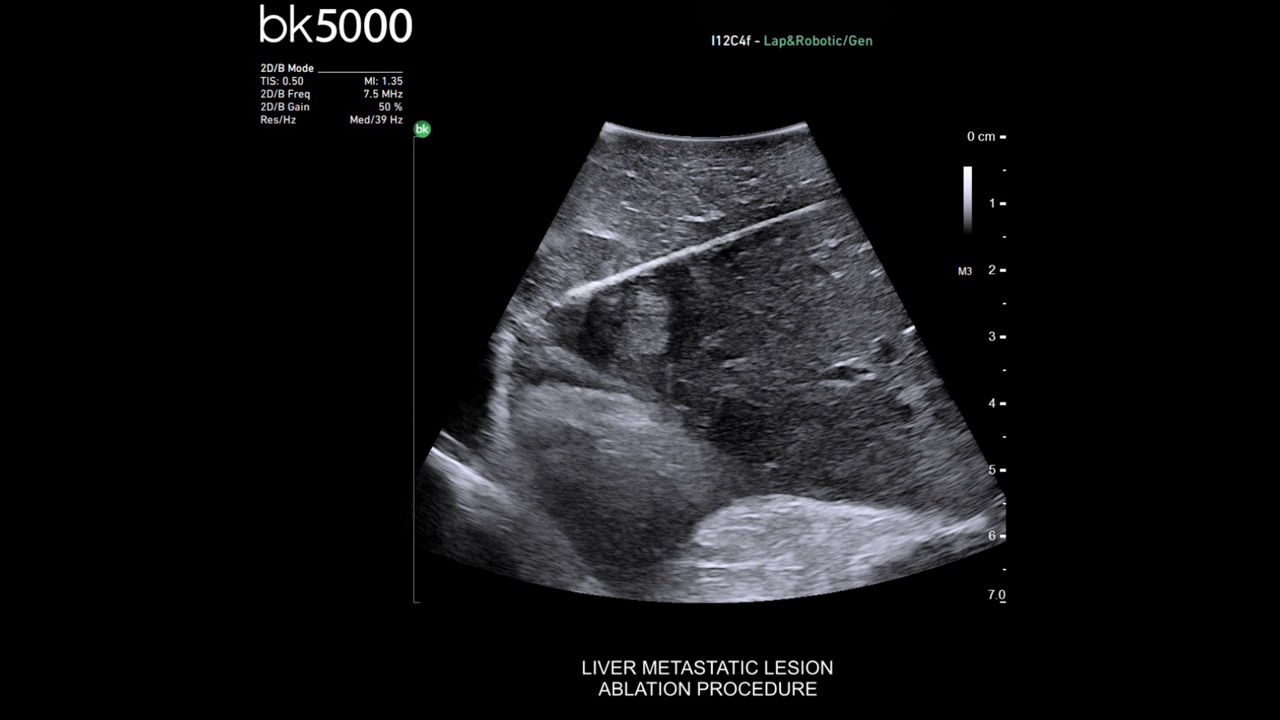

Ablation imaging

Active imaging supports liver and pancreas ablation procedures by helping you visualize lesions and blood vessels, identify healthy tissue vs. tumor, and guide and view needle placements.

Use intraoperative ultrasound to:

• Enable visualization of disease staging at the time of surgery with excellent image quality.

• Guide and view needle placements in real-time.

• Verify your planned results by assessing pre- and post-ablation images together.